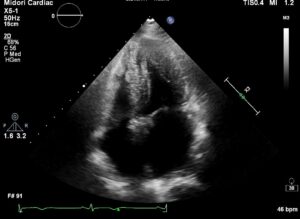

20210818_examination_05